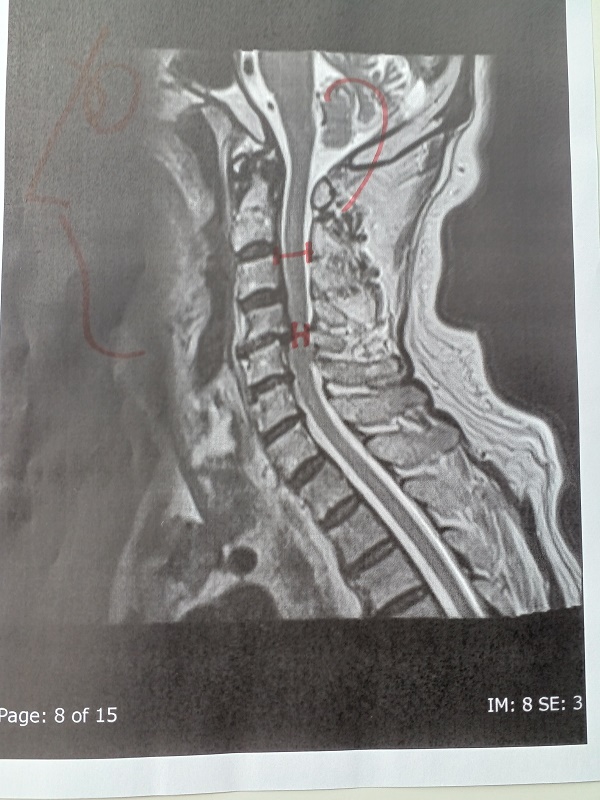

0.頚椎症は、進行せず安定。(働かなくなると首の筋肉が衰えて進行するかも)

写真11.頸椎の4番と5番の間の神経が、通常の半分まで狭められています。

写真12.頸椎の断面。赤の斜線部分が、半分つぶれています。